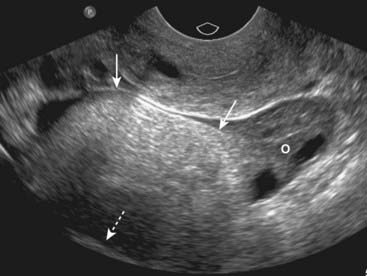

Figure 19-22 Pelvic inflammatory disease, sagittal and transverse views, US.

A, A fluid-filled and dilated fallopian tube (FT) containing pus and debris (solid black arrow) representing a pyosalpinx is demonstrated. B, Due to progressive inflammation, there is fusion of a dilated and tortuous fallopian tube (solid black arrow, FT) and the adjacent ovary (solid white arrow, OV) producing a tubo-ovarian complex.